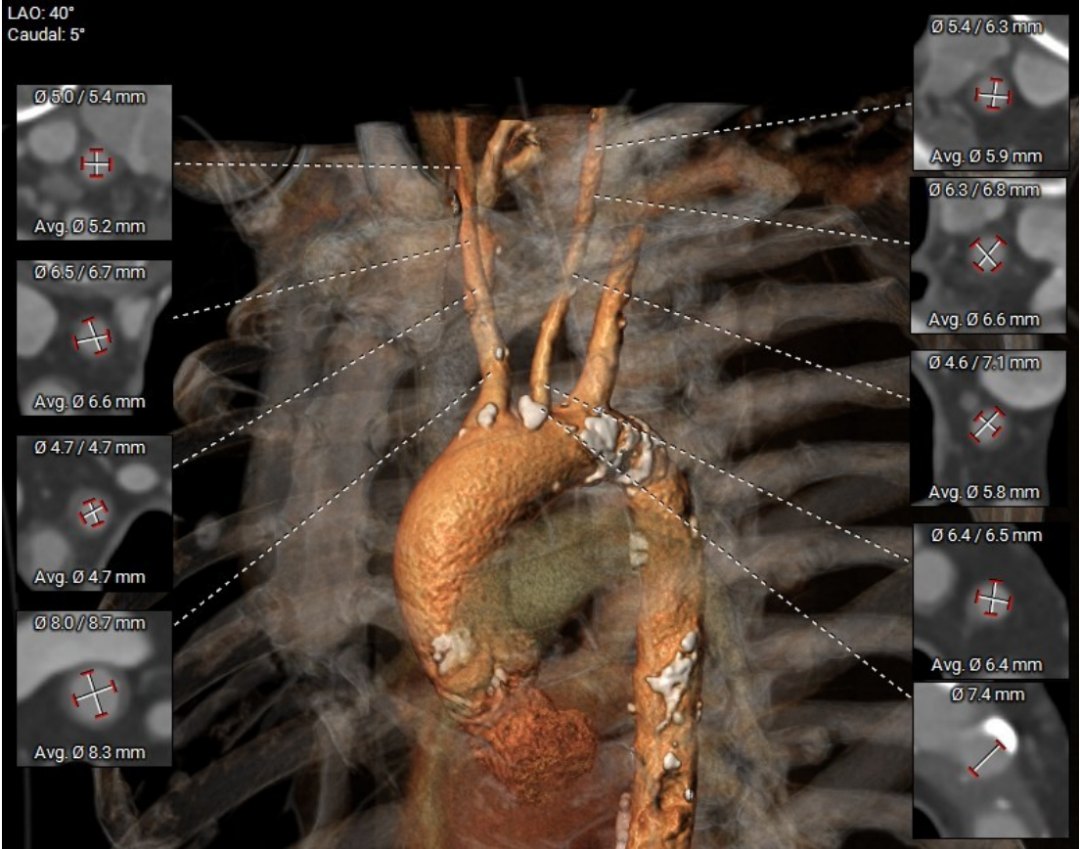

术前CT评估

根部结构:Type1二叶瓣(L-R型),左右之间纤维钙化融合嵴,轻中度钙化伴瓣叶增厚,瓣环:22.0mm,左室流出道 :22.1mm,瓦氏窦:33.1mm,瓣上限制区(supra-8mm):21.5mm,极小心腔。

钙化积分:273mm³

冠脉风险评估

左冠高度:16.1mm

右冠高度:18.5mm

左右冠高度可,瓣叶长度可,综合评估左右冠阻挡风险低。